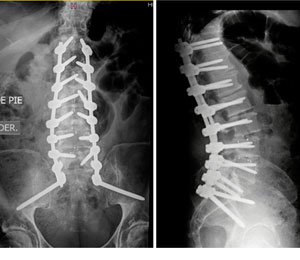

Me diagnosticaron escoliosis cuando tenía 13 años, en el año 2010 y ese mismo año me operaron en el mes de octubre. Al inicio, no me gustó la idea de la operación porque interfería con algunos planes que ya tenía en mente, pero sabía que si quería estar bien, tenía que sacrificarlos porque más importante era mi salud. No muchos doctores saben de esta enfermedad, gracias a Dios conocí al Dr. Cárdenas que fue muy amable y amigable conmigo y me explicó con todo detalle como sería la intervención; así que más que miedo, sentía emoción porque llegara el día.

Después de mi operación, solo estuve internada 4 días. Tengo 11 tornillos en mi columna y ya llevo 5 años de operada; vivo una vida normal y soy feliz.